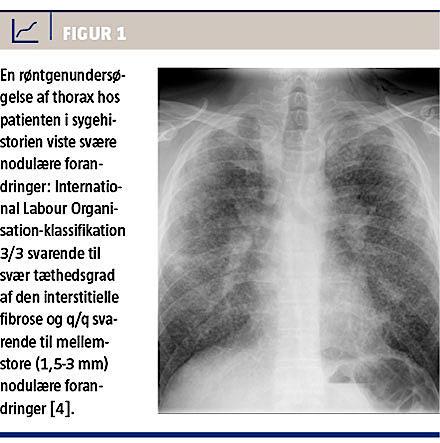

Objektivt viste en stetoskopi af lungerne normale forhold, men en røntgenundersøgelse af thorax viste svære nodulære forandringer: International Labour Organisation 3/3, q/q (Figur 1) [5]. Der blev målt følgende værdier: udvidet lungefunktion med forceret eksspiratorisk volumen i første sekund: 2,3 l (58%), forceret vitalkapacitet: 3,9 l (81%), indeks: 58%, total lungekapacitet: 80% og diffusionskapacitet: 54% (Figur 2). High resolution-CT (HRCT) af thorax viste symmetrisk hilær lymfadenopati og enkelte lymfekirtler med forkalkninger. Herudover blev der ved PET fundet positiv opladning af samtlige lymfekirtler.